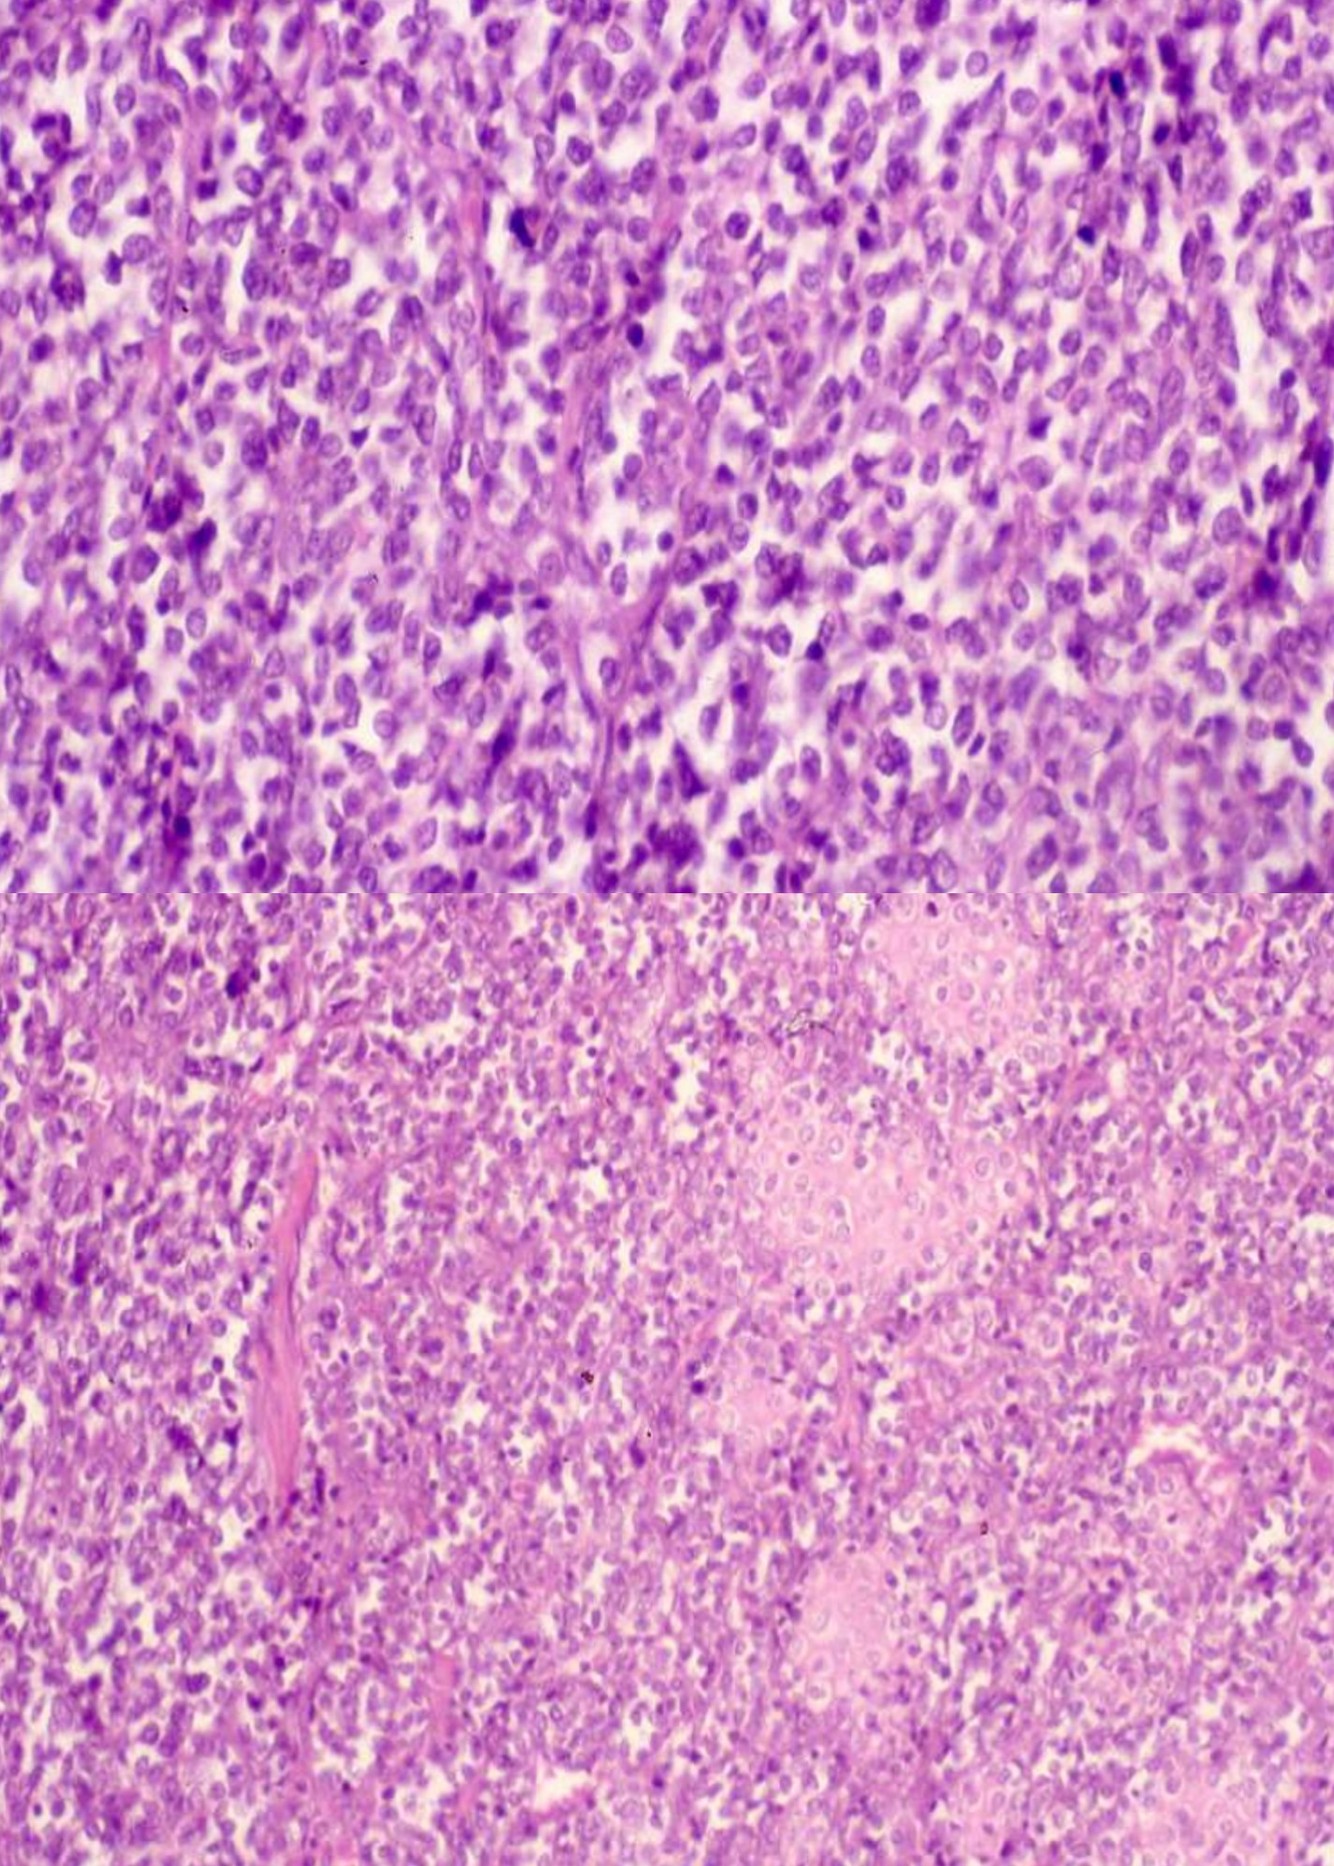

OSTEOSARCOMA subtypes (5)

OSTEOSARCOMA

CONVENTIONAL OSTEOSARCOMA

TELANGIECTATIC OSTEOSARCOMA

SMALL CELL OSTEOSARCOMA

SURFACE OSTEOSARCOMA